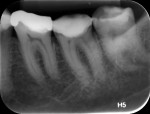

A 56-year-old, female Caucasian patient presented to the office complaining of spontaneous, pulsing pain in the left mandible region, which did not cease with the use of analgesics and anti-inflammatories. She had a negative response to the tests of apical palpation and vertical and lateral percussion on all of the teeth in this quadrant, and thermal tests showed an exacerbated, long-duration positive response to both cold and heat on tooth No. 37. Regarding the other teeth in the quadrant, a slight, short-duration positive response was shown to cold, with a negative response to heat.

According to the classification system of the American Endodontics Association, tooth No. 36 had a pulpal and periapical diagnosis of irreversible inflammatory pulpitis with normal periapex, for which endodontic treatment is indicated (Figure 1 through Figure 3).6

To complete the procedure, the Fillapex MTA cement was prepared and introduced into the canals using the main gutta-percha cones (Figure 6). The excess material from the cones was cut using a heat transfer system (Touch'n Heat Sybron Endo) and cold-compressed vertically. The pulp chamber was sealed with photopolymerizable composite resin, and the patient was sent to her dentist for a definitive restoration of the dental element (Figure 7). After 17 months, the patient returned for a control consultation, and an evaluation of her x-ray images indicated endodontic success characterized by the absence of signs and symptoms, the physiologic function of the tooth, the normality of the periapex, and the reabsorption of the surplus Fillapex MTA cement (Figure 8).